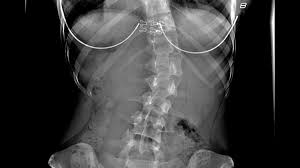

Patient Stories Scoliosis And Spine Associates from www.scoliosisassociates.com Carreira no mma ultimate fighting championship. Shane burgos was fighting his fourth straight fight from his own home state of new york. Viewed from the side, the normal spine takes the form of an elongated s, the upper back bowing outward and the lower back curving slightly inward. As of april 26, 2021, he is #9 in the ufc featherweight rankings. Shane burgos is a top ufc fighter. As a teenager, burgos underwent surgery for severe scoliosis and doctors told him he'd never be able to fight again. Ufc fighter shane burgos overcame scoliosis at age 16. Hey, i got mild scoliosis (spine curves) it doesn't affect me but in the future i want to turn pro in mma.

Thank you so so much for this answer! The disease took a grave turn when he. While complex in nature, medical breakthroughs are leading to exciting new treatment options that allow children with this condition to enjoy rich, full lives. Mount sinai doctors manhasset 1155 northern boulevard manhasset, ny 11030. Learn how rich is he in this year and how he spends money? Scoliosis is a musculoskeletal disorder that results in a curved spine. Viewed from the side, the normal spine takes the form of an elongated s, the upper back bowing outward and the lower back curving slightly inward. 1 mixed martial arts career. I have a way smaller tilt and feel it all the time. Shane hurricane burgos is an american professional mixed martial artist in the ufc featherweight division. Mount sinai doctors manhasset 1155 northern boulevard manhasset, ny 11030. Carreira no mma ultimate fighting championship. I started training to be a mixed martial arts (mma) fighter when i was 15.

Three in every 1,000 people end up developing scoliosis at some point. Viewed from behind though, the spine should appear as a straight line from the base of the neck to the tailbone. As a teenager, burgos underwent surgery for severe scoliosis and doctors told him he'd never be able to fight again. The angle of the curve may be small, large, or somewhere in between. Edson barboza, with official sherdog mixed martial arts stats, photos, videos, and more for the featherweight fighter from.

Mount sinai doctors manhasset 1155 northern boulevard manhasset, ny 11030. Joshu shane burgos has studied for 9 years under sensei jose montes, the owner/instructor of tiger schulmann's mixed martial arts (tsmma) in vails gate, ny. Scoliosis is a sideways curvature of the spine. Edson barboza, with official sherdog mixed martial arts stats, photos, videos, and more for the featherweight fighter from. Three in every 1,000 people end up developing scoliosis at some point. (joshu means assistant mixed martial arts instructor. But after refusing to give up on his goal, burgos is now earning plenty of admirers in the ufc. Also learn how he earned most of networth at the age of 29 years old? While complex in nature, medical breakthroughs are leading to exciting new treatment options that allow children with this condition to enjoy rich, full lives. I know nate quarry had a slipped disc and back surgery, tito ortiz had back surgery, and. He's had scoliosis surgery and he's still out there fighting. The squeaks have been silenced for about a year now, but not before shane burgos risked his health to pursue his dream. Original poster 1 point · 1 year ago.